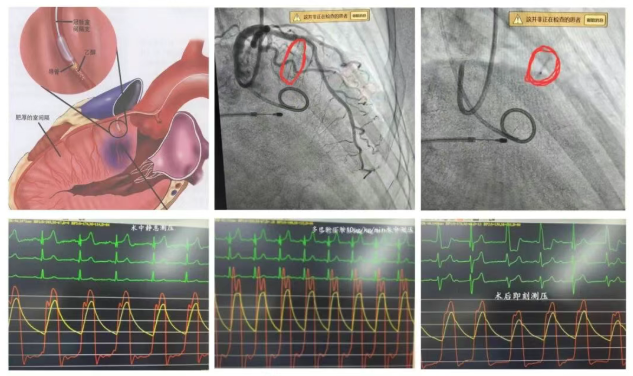

该女性患者74岁,反复晕厥,曾在外院就诊,治疗效果不佳,后慕名来到镇江瑞康医院心内科救治。心脏超声显示:室间隔厚度18mm,左室后壁12mm,LVOT Vmax 344cm/s,PG:47mmHg,轻度SAM现象,瑞康医院心内科学科带头人严金川教授组织全科讨论,一致认为该患者需要做多巴酚丁胺激发试验明确梗阻情况,给予患者10ug/kg/min多巴酚丁胺后LVOT Vmax 620 cm/s,PG:155mmHg,激发试验明显阳性,该患者属于隐匿型肥厚梗阻型心肌病。

目前治疗该类疾病方法有四种,药物、外科手术、双腔起搏及化学消融治疗。经过团队讨论后认为微创介入化学消融比较安全可靠。术中测得静息情况下流出道压差(PG):30mmHg,多巴酚丁胺10ug/kg/min,术中测压PG:85mmHg,冠脉造影显示供应室间隔肌肉的第一间隔支血管清晰,采用over-the-wire球囊阻断第一间隔支血流,将无水酒精2ml注入远端室间隔支,术后即刻测得PG:26mmHg,30分钟后心脏超声显示:PG:11mmHg,明显降低,手术圆满成功,术后一周复查心脏超声显示:LVOT Vmax 149cm/s,PG:9mmHg,这一结果为患者的后续康复奠定了良好基础。